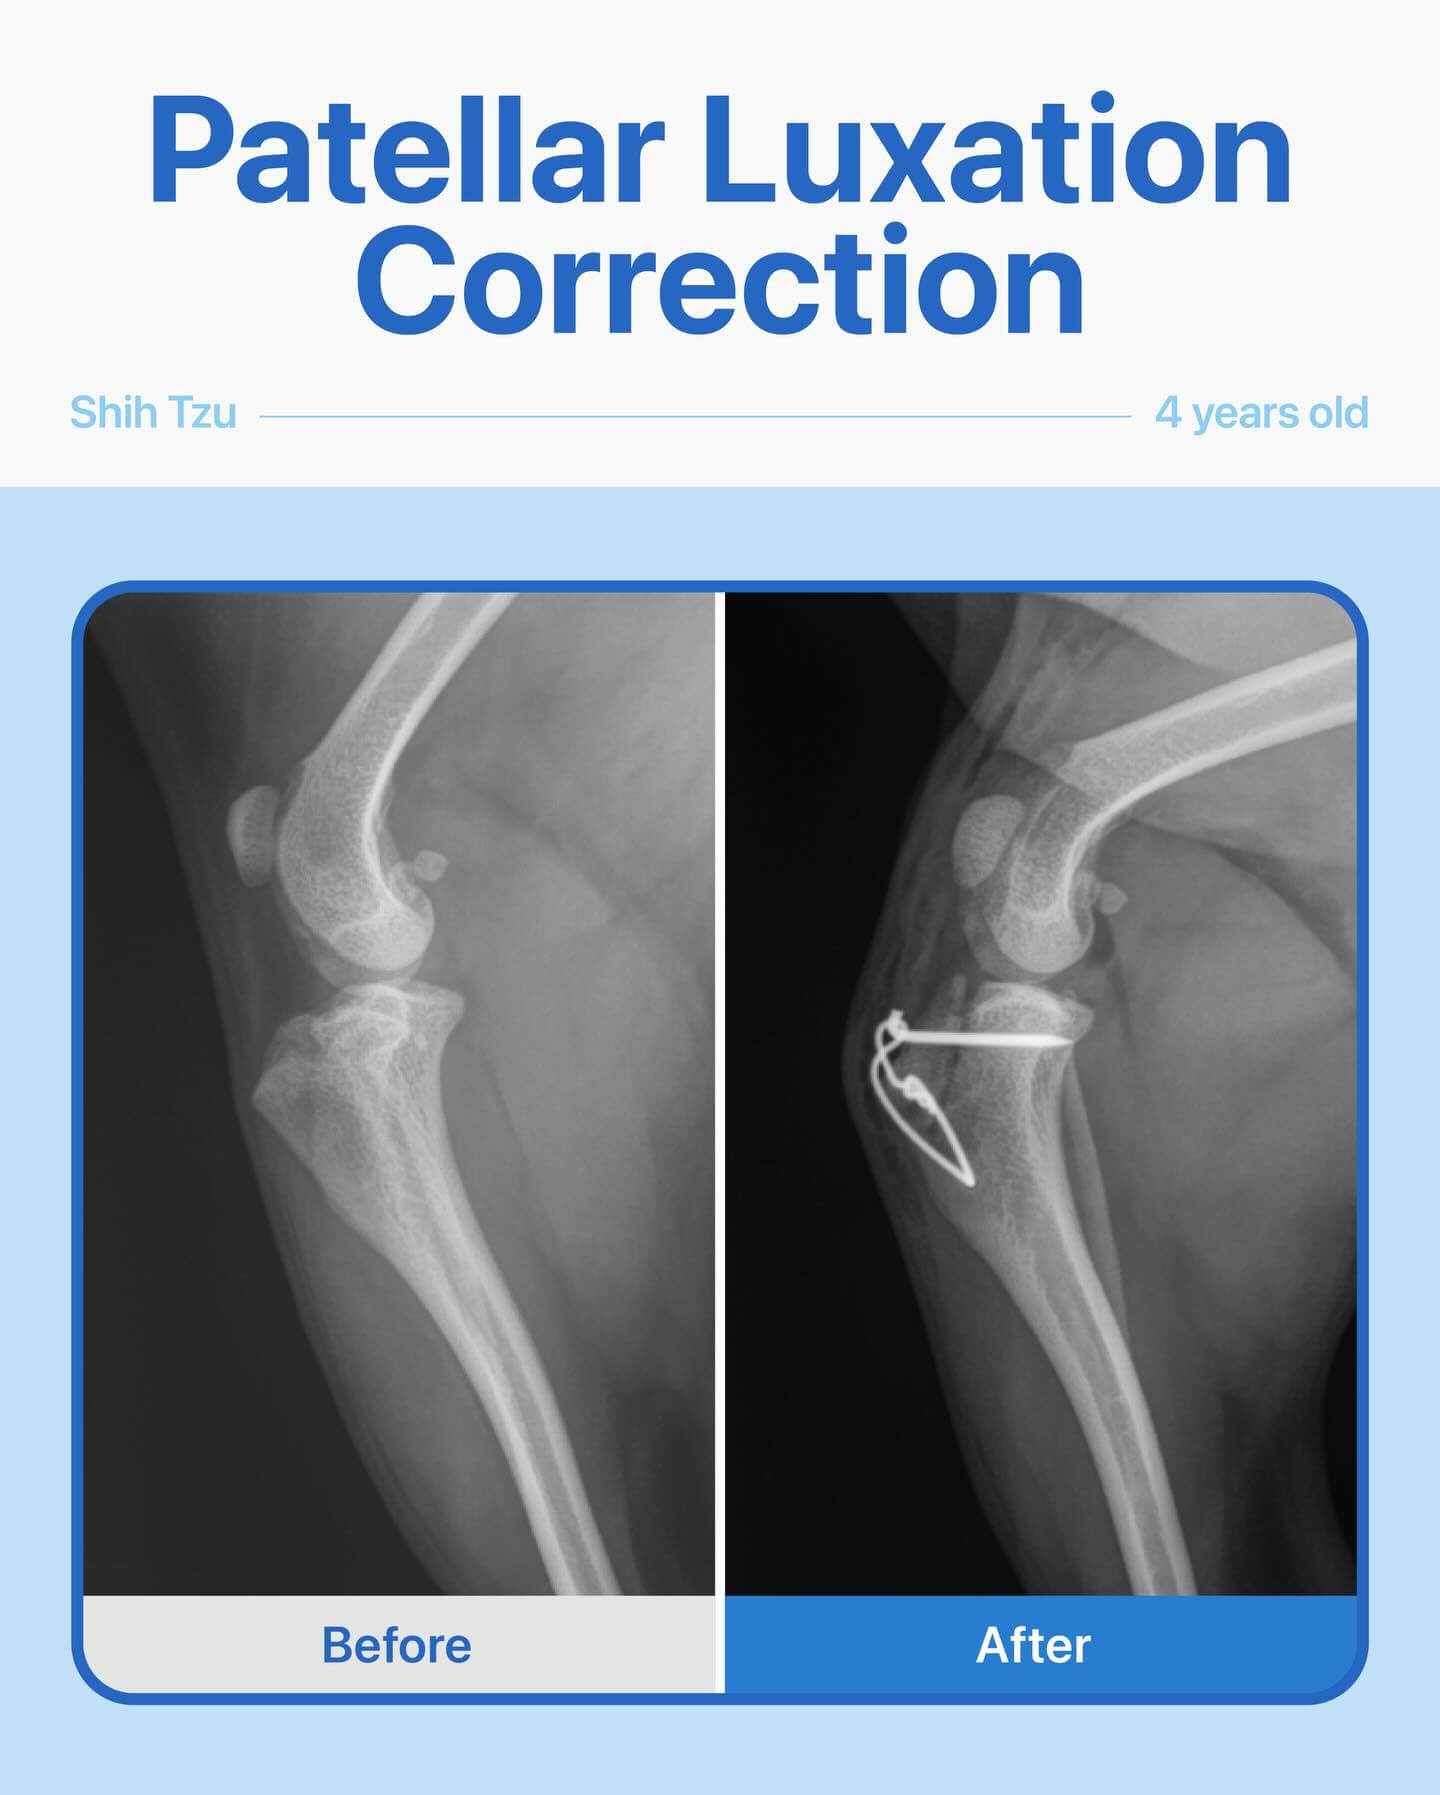

This sweet Shih Tzu came to us limping on her right hind leg, showing clear signs of discomfort and pain. After a thorough physical exam and radiographs, we discovered her kneecap (patellar) had slipped out of its normal position — a condition known as patellar luxation. Our team performed a patellar luxation repair surgery, and everything went smoothly. Throughout her recovery, she did wonderfully, and now she’s back to being her playful, happy self, moving comfortably and without pain again. Moments like this are why we love what we do.